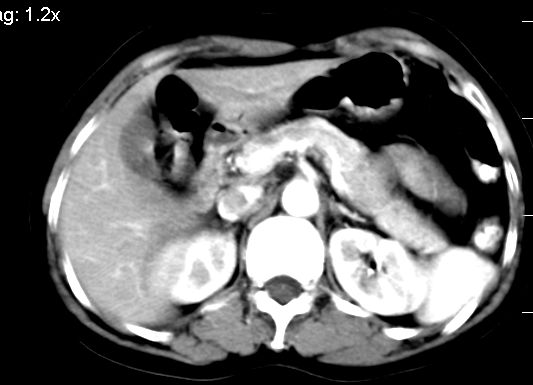

标题: CT10752:F,52岁,反复上腹部疼痛,平扫+增强. [打印本页]

f、52岁,反复上腹部疼痛2年。肺结核病史10多年,胸片双上肺结核纤维化。

ct表现:

肝大小形态未见异常,肝内外胆管无扩张,肝s8段见一动脉期明显血管样强化结节,门脉期呈高密度,延迟期呈等密度,胆囊不大,增强扫描见胆囊及胆囊颈管壁增厚,有强化。

双肾灌注良好,代谢增快,动脉期肾盂见造影剂,左肾下极背侧见一略低密度病灶,延迟期见似不强化囊肿,双侧肾上腺未见异常。

胰腺及脾未见异常。肾门水平腹膜后见小淋巴结。腹腔未见积液征象。

诊断:

1、胆囊炎(轻度)。

2、肝s8段结节,考虑小血管瘤。

3、左肾下极低密度灶,考虑囊肿可能性大,建议随访,除外小肾癌(无强化可以基本除外)。

4、目前ct表现尚不能解释患者上腹部疼痛,建议上消造影检查,除外胃炎等疾患。